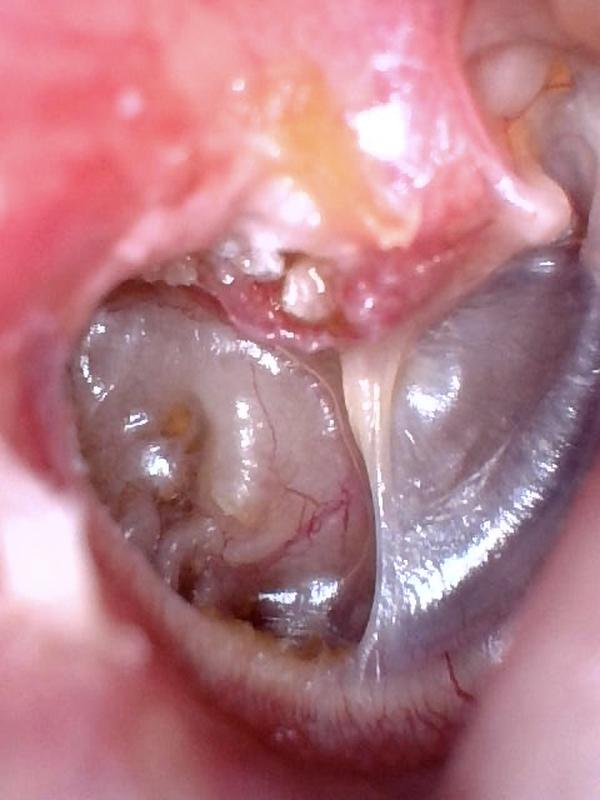

Cholesteatoma